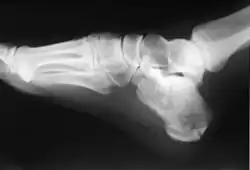

Skiagrafie (z řeckého skiá (σκιά) – „stín“ a grafie – „záznam“) je technika zobrazení lidských tkání, využívající rozdílnou hodnotu pohlcení procházejícího svazku rentgenového záření v různých tkáních. Ze získaného obrazu pak lze ohodnotit jednak vnitřní stavbu vyšetřovaného orgánu, jednak jeho případná poranění. Pokud je obraz orgánu pouze pozorován bez zachycení na film nebo jiné záznamové médium, mluvíme o skiaskopii.

Nejčastěji je skiagrafie využívána pro vyšetření kostí a zubů. Dříve časté (i screeningové) snímkování plic je nahrazováno jinými metodami.